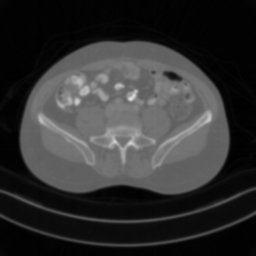

| Ground Truth | Input | DDS-100 [chungdecomposed] | DDS-200 [chungdecomposed] | NERD-P (Ours) |

![]() |

| PSNR = dB | PSNR = 14.56 dB | PSNR = 37.42 dB | PSNR = 37.81 dB | PSNR = 39.15 dB |

Main results: In Table 1, we present quantitative results and in Figure 2, we show visualizations in the axial, coronal, and sagittal planes. Our methods consistently outperform the second-best baseline across most views, achieving nearly 1 dB higher PSNR on average. Despite incorporating a few additional input updates to enforce data consistency, our method reaches competitive performance with only 30 sampling steps. Based on the visualizations, we observe that DDS introduces slight artifacts along the horizontal direction, particularly noticeable in the coronal and sagittal views. In contrast, our method produces cleaner reconstructions with fewer artifacts in these orientations.